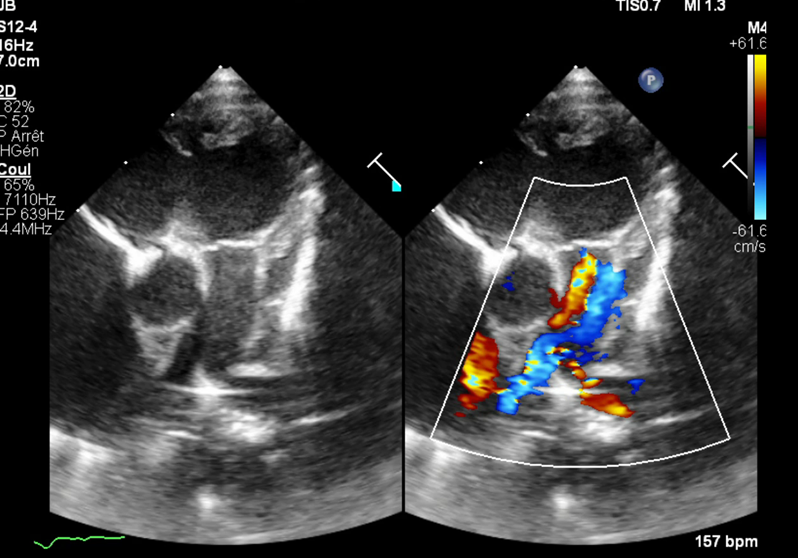

A 5-day-old newborn, born at 36 weeks of gestation to a mother with preeclampsia, presented with poor initial adaptation, including no movement, no cry, and a heart rate below 100 bpm. Echocardiography revealed a major defect in the atrioventricular valve with torrential regurgitation, tricuspid atresia with absence of flow through the right ventricular outflow tract, and a well-developed pulmonary artery. The newborn was started on prostaglandin therapy, which allowed for pulmonary perfusion with oxygen saturation between 85-90%. A multidisciplinary team discussed three possible management options: dilation of the right ventricular outflow tract, Starnes procedure with Blalock shunt, or discontinuation of prostaglandin therapy.

- *Echocardiography Findings:*

- Major defect in atrioventricular valve with torrential regurgitation

- Tricuspid atresia with absence of flow through the right ventricular outflow tract

- Well-developed pulmonary artery

- Large atrial septal defect (ASD) with right-to-left shunt

- Large patent ductus arteriosus (PDA) with left-to-right shunt

- No left-sided anomalies